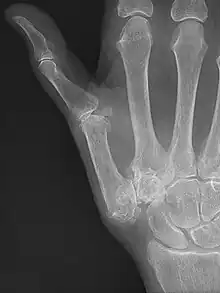

![]() Imagen radiográfica que muestra signos de artrosis de la articulación trapeciometacarpiana. | ||